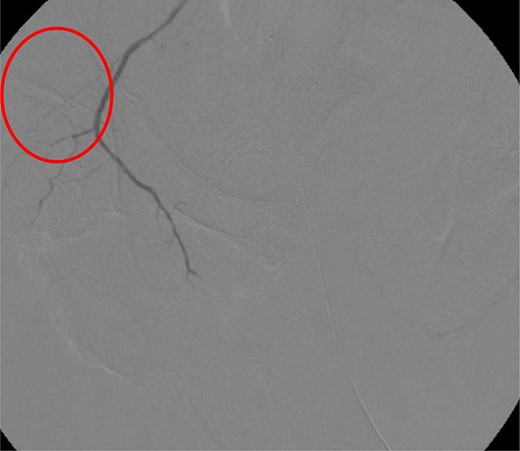

CT abdomen/pelvis with contrast was performed and a blush of contrast was noted posterior to the right pubic bone. Prior to taking patient for exploratory surgery, he was transferred to the interventional radiology suite where a pelvic angiogram was performed revealing an abnormal blush localized to the distal branches of the right iliolumbar artery (Fig. 2). Delayed phase of the angiogram demonstrated early venous filling consistent with a traumatic arteriovenous fistula which was embolized with 300–500 µ of embospheres and three 3 × 2 microcoils (Figs 3 and 4).

CT angiogram demonstrating microcoil embolization of AV fistula.

CT angiogram demonstrating successful embolization of AV fistula.

After resolution of the traumatic arteriovenous fistula (Fig. 2), a second blush from the right distal internal pudendal artery was identified and successfully treated with Gelfoam slurry. Subsequently, patient underwent exploratory laparotomy which revealed mesenteric and retroperitoneal hematomas. He also underwent craniotomy for evacuation of the subdural hematoma and open reduction internal fixation of the anterior and posterior pelvis. After discharge in fair condition to a subacute rehabilitation facility, patient developed a deep venous thrombosis managed by Coumadin.